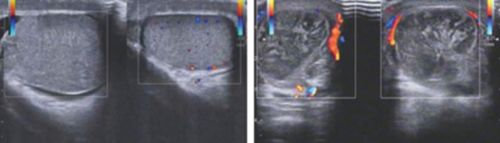

(二)彩色多普勒:病程早期,病变程度尚轻,患侧睾丸内仍可见少许彩色血流信号;病程进展后,患侧睾丸内无明显血流信号,健侧睾丸内可见小条状彩色血流信号。

A.双侧睾丸纵切面CDFI 对比示意图,左侧睾丸大小正常,内可见彩色血流信号;右侧睾丸增大,内无彩色血流信号,鞘膜腔内可见积液。

B.右侧睾丸横切面CDFI 示意图,右侧睾丸内无血流信号。